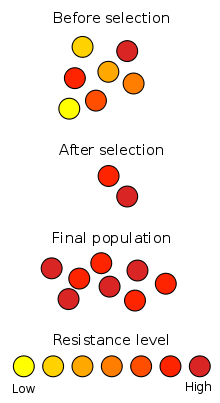

Natural selection is seen in action in the development of antibiotic resistance in microorganisms. Since the discovery of penicillin in 1928, antibiotics have been used to fight bacterial diseases. The widespread misuse of antibiotics has selected for microbial resistance to antibiotics in clinical use, to the point that the methicillin-resistant Staphylococcus aureus (MRSA) has been described as a "superbug" because of the threat it poses to health and its relative invulnerability to existing drugs.[76] Response strategies typically include the use of different, stronger antibiotics; however, new strains of MRSA have recently emerged that are resistant even to these drugs.[77] This is an evolutionary arms race, in which bacteria develop strains less susceptible to antibiotics, while medical researchers attempt to develop new antibiotics that can kill them. A similar situation occurs with pesticide resistance in plants and insects. Arms races are not necessarily induced by man; a well-documented example involves the spread of a gene in the butterfly Hypolimnas bolina suppressing male-killing activity by Wolbachia bacteria parasites on the island of Samoa, where the spread of the gene is known to have occurred over a period of just five years [78][79]